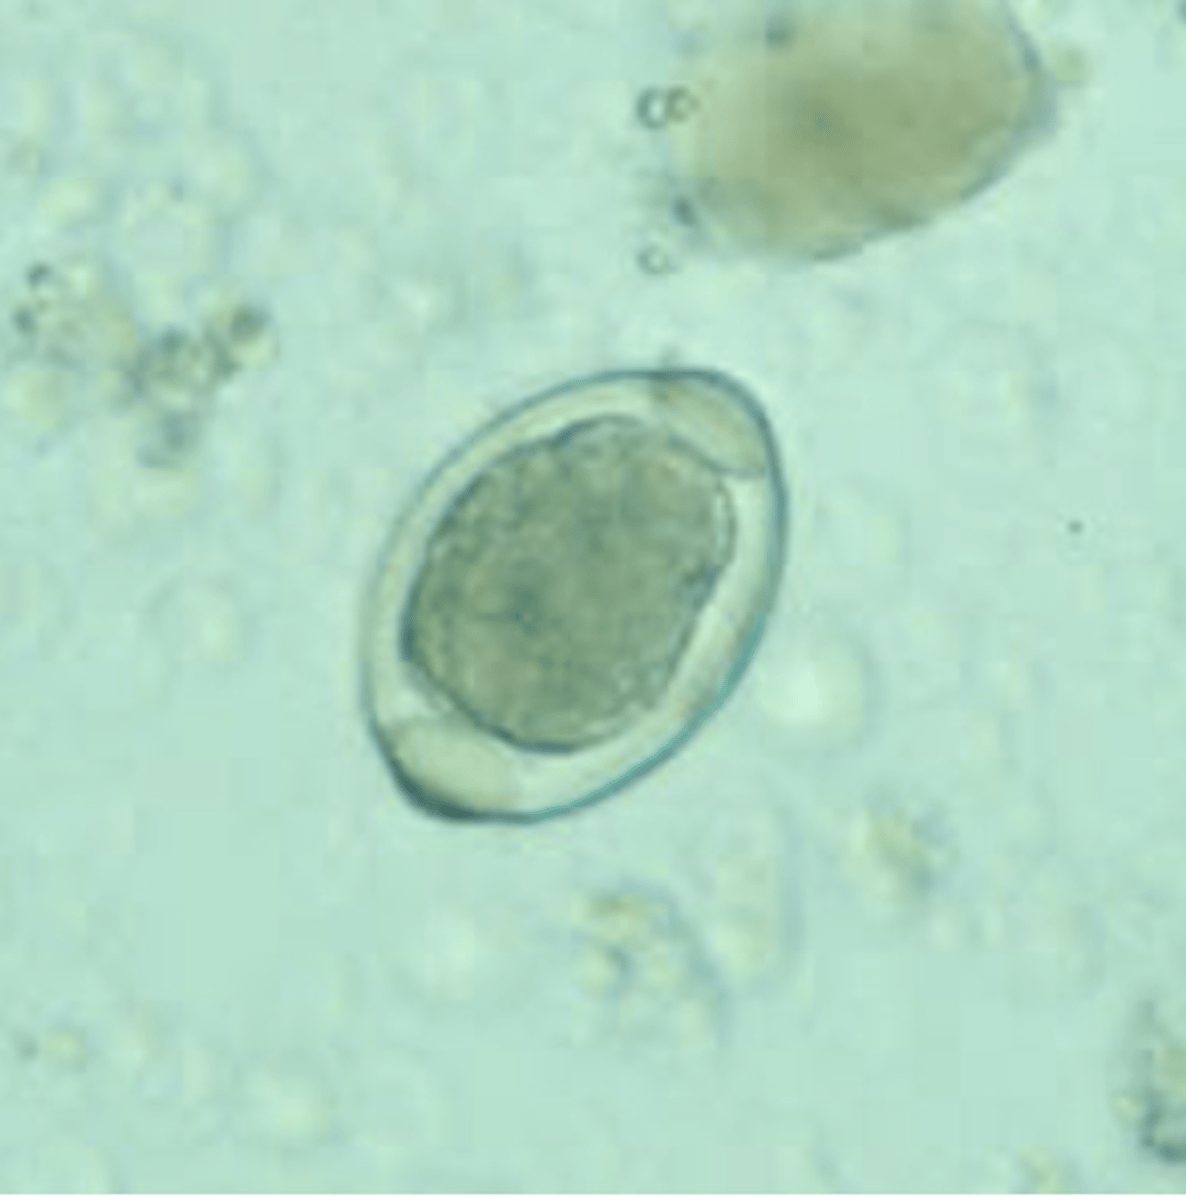

Taenia spp. egg